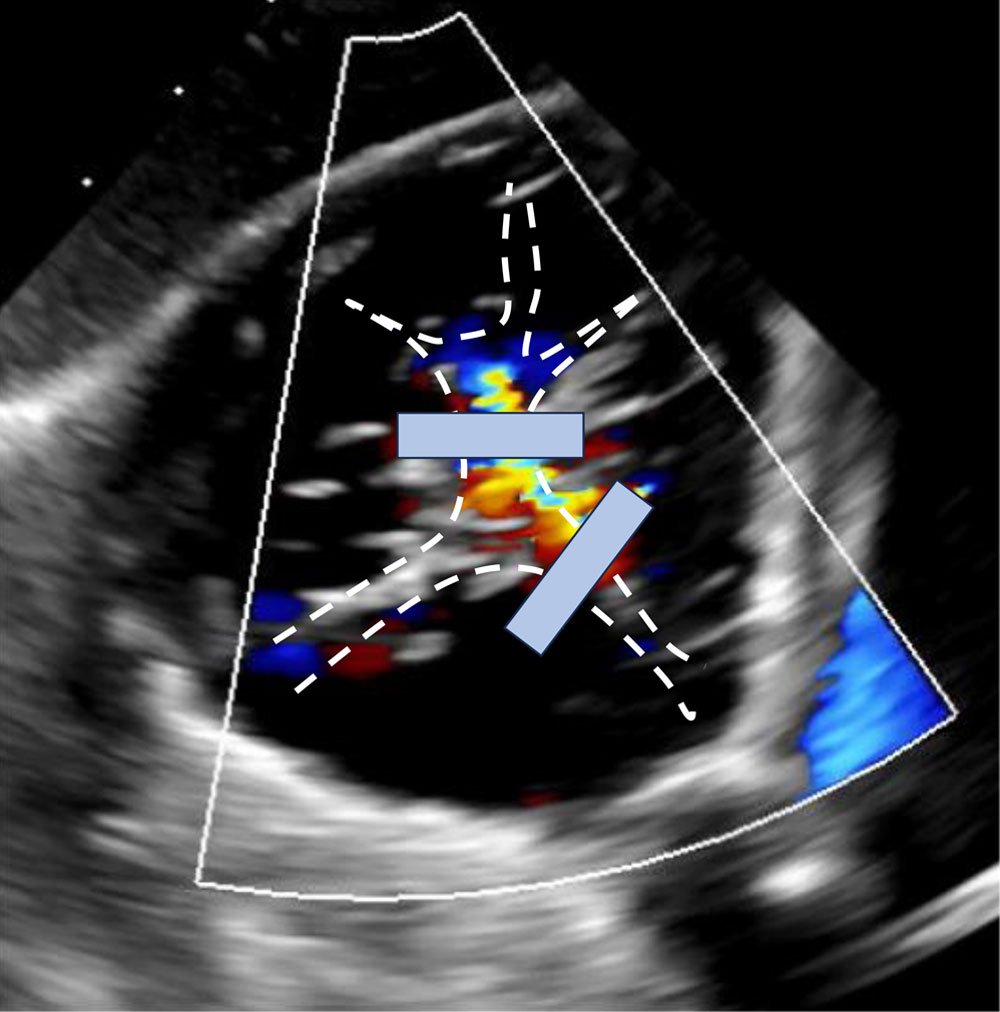

The interventional team decided to perform T-TEER using two TriClip XT devices.

- Clover technique: First device implanted anterior-septal, second posterior-septal, to address both regurgitant jets

- Bicuspidalization technique: Bicuspidalization with two anterior-septal devices (“zipping technique”)

We aimed for a Clover technique in order to reduce the posterior regurgitation jet adequately. However, bicuspidalization also often reduces posterior regurgitation jets due to annular reduction effects of TEER and subsequent reverse remodelling of the right ventricle.

After the first TriClip XT implantation, sufficient TR reduction was achieved with only mild residual TR posterior to the first TEER device.

Despite this adequate TR reduction, we aimed for a second TEER device implantation in Clover technique.